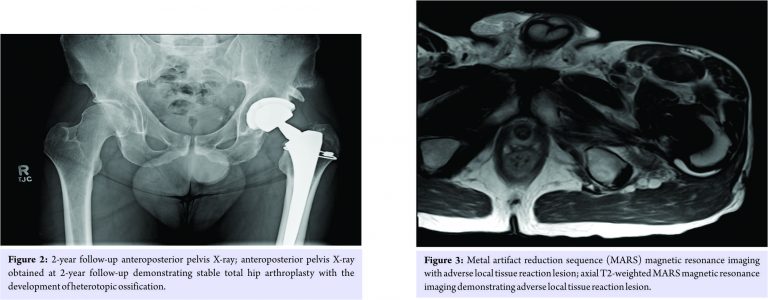

Routine post-operative monitoring was uneventful. At his 6-week follow-up, he was progressing well with stable radiographs. Per our usual THA recommendations, the patient was advised to progress with non-impact loading activities. At his 3-month follow-up, Harris hip score pain (HSS-P) question was 1 out of 6 (no pain), and UCLA activity score (UCLA-AS) was 9 out of 10 (sometimes participating in impact sports). The patient noted that he participated in impact-loading activities, including jogging and hiking. He was again advised of the optimal activity level for THA patients, emphasizing non-impact activities (e.g., bicycling and swimming). At his 12-month follow-up, HSS-P and UCLA-AS remained 1 and 9, respectively, and radiographs remained stable. Discussion regarding activity was the same as at the 3-month follow-up. Routine 5-year follow-up was planned. Voluntary recall of his femoral stem occurred 2 years postoperatively. He was informed of the risks of ALTR associated with this stem and invited for follow-up, HHS-P and UCLA-AS were again 1 and 9, respectively. Radiographs demonstrated a well-fixed THA in appropriate alignment without evidence of periprosthetic osteolysis, calcar femorale rounding, or polyethylene wear (Fig. 2). Baseline serum Co (4.8 mcg/L, reference normal <3.9), serum Cr (<1.0 mcg/L, normal ≤5.0), erythrocyte sedimentation rate (2 mm/hr, normal <20), and C reactive protein (<3.0 mg/L, normal <10.0) were obtained. Per protocol at our institution for evaluating asymptomatic patients with this recalled implant and with elevated serum Co, a cross-sectional anatomy study by ultrasound scan was obtained, demonstrating a 2.7 × 1.2 cm fluid collection anterior to the hip without other sequelae of ALTR. He was again advised against impact loading activities.

Annual follow-up was planned to monitor for any clinical deterioration or progression of ALTR. At 34-month follow-up, serum Co had increased to 6.2 mcg/L. HHS-P and UCLA-AS remained 1 and 9. Due to increase in Co level, MRI with metal artifact reduction sequence (MARS) was obtained and demonstrated a 3.6 × 0.7 cm fluid collection posterior to the hip (Fig. 3), but without other sequelae of ALTR. At 41-month follow-up, serum Co reached 7.6 mcg/L. HHS-P was now 2 (slight or occasional pain, with no compromise inactivity). The patient stated that he had participated in mountain hiking shortly before this Co level was obtained. Repeat MARS MRI demonstrated a 4.0 × 0.8 cm fluid collection posterior to the hip, without other sequelae of ALTR. After further counseling, the patient elected revision arthroplasty, but deferred surgery until his work calendar allowed. In the interim, he planned stationary bicycling and swimming for fitness activity. 45 months after index THA, the patient presented for pre-operative evaluation. He had eliminated high-impact activities. He wished pre-operative re-check of serum Co, which showed a decrease to 5.3 mcg/L. With continued satisfactory THA clinical outcome, the patient deferred revision surgery, opting to maintain non-impact-loading activity level and monitor serum Co. At his 4.5-years follow-up visit, he remained satisfied with his THA, with HHS 96, HHS-P 2, UCLA-AS 8 (very active, but no impact sports), and Co 2.2 mcg/L, and was bicycling and swimming for fitness. The patient wished to continue non-impact-loading activity level and monitor symptoms and serum Co. He recently had his Co level re-checked at 5.0 years postoperatively, and it was 1.2 mcg/L.